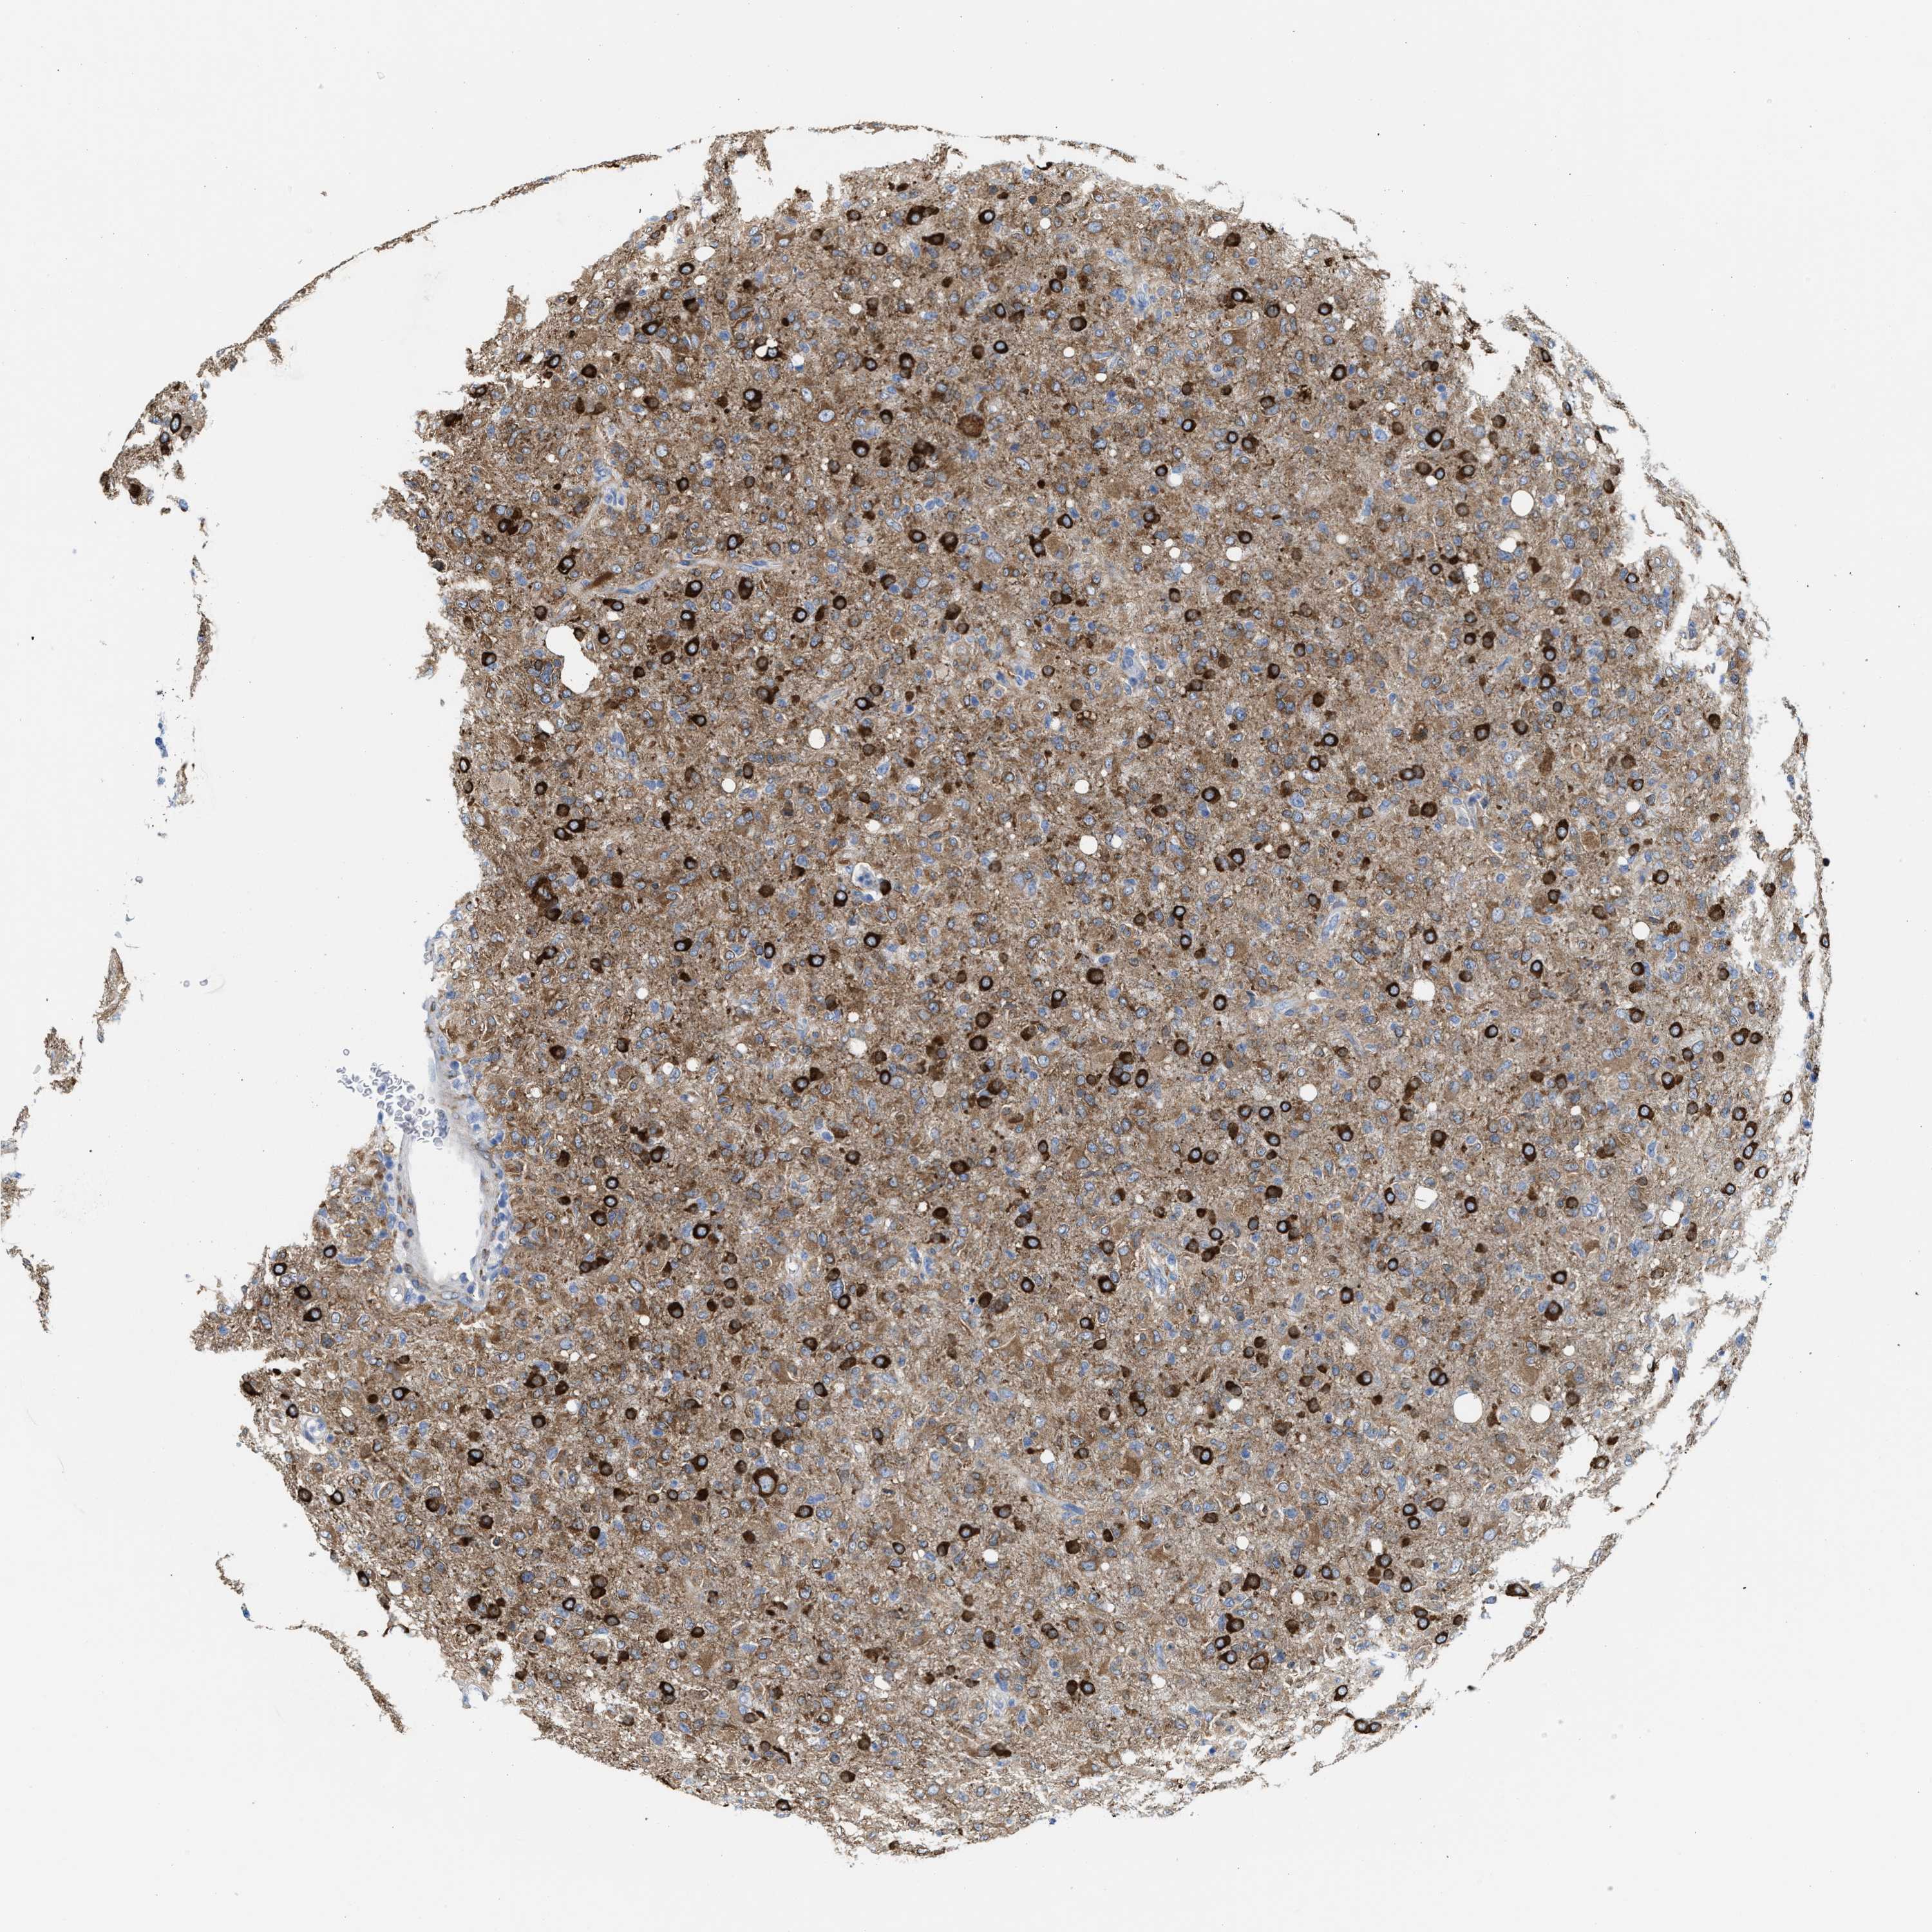

GLIOMA - Protein expressioni

A mouse-over function shows sample information and annotation data. Click on an image to view it in a full screen mode. Samples can be filtered based on level of antibody staining by selecting one or several of the following categories: high, medium, low and not detected. The assay and annotation is described here.

Note that samples used for immunohistochemistry by the Human Protein Atlas do not correspond to samples in the TCGA dataset.

Antibody stainingi

Antibody staining in the annotated cell types in the current human tissue is reported as not detected, low, medium, or high, based on conventional immunohistochemistry profiling in selected tissues. This score is based on the combination of the staining intensity and fraction of stained cells.

Each image is clickable and will lead to virtual microscopy that enables deeper exploration of all samples and also displays staining intensity scores, fraction scores and subcellular localization as well as patient and tissue information for each sample.

Antibody HPA019324

Staining

High

Medium

Low

Not detected

Intensity

Strong

Moderate

Weak

Negative

Quantity

>75%

75%-25%

<25%

None

Location

Nuclear

Cytoplasmic/membranous

Cytoplasmic/membranous,nuclear

Glioma, malignant, High grade

Glioma, malignant, Low grade